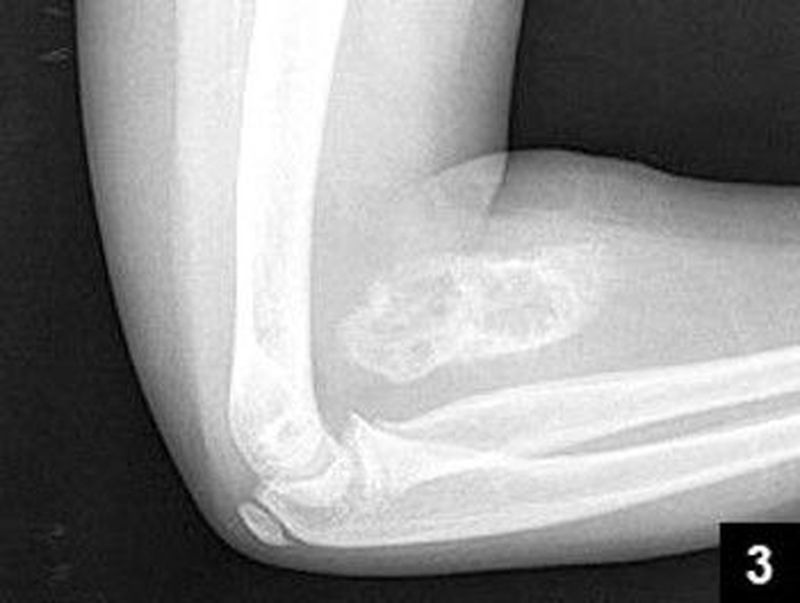

Myositis ossificans

Orthopaedics

Fracture

Complication

Supracondylar